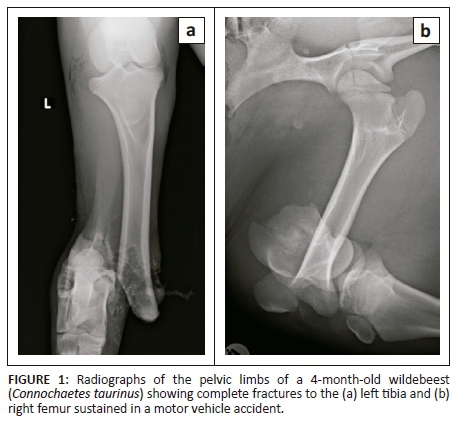

A fractious 4-month-old female wildebeest (Connochaetes taurinus) weighing 70 kg was presented for surgical fixation of bilateral pelvic limb fractures resulting from a motor vehicle accident (Figure 1). Anaesthesia was induced with medetomidine (0.01 mg/kg; 40 mg/mL, Kyron Laboratories, South Africa) and ketamine (5 mg/kg; 100 mg/mL, Ketamine Fresenius, Fresenius Kabi, Midrand, South Africa) intramuscularly. The wildebeest was intubated using a 10 millimetre internal diameter PVC endotracheal tube and anaesthesia was maintained with isoflurane (Isofor, Safeline, Weltevreden Park, South Africa) in oxygen (end-tidal concentration 0.8% - 1.1%). Intravenous fluid support was provided in the form of an isotonic crystalloid (lactated Ringers solution, 10 mL/kg/h) and a hydroxyethylated starch colloid (two 10 mL/kg boluses in the first 3 hours of anaesthesia; Voluven; Fresenius Kabi, Midrand). Clinical examination under general anaesthesia revealed a water-hammer pulse, cold extremities and marked pallor. Clinical parameters and arterial blood gas analysis results are shown in Table 1. Direct arterial blood pressure was satisfactory 2 h after induction of anaesthesia but decreased thereafter to levels associated with hypoperfusion in mammalian species (mean arterial blood pressure less than 60 mmHg [Dugdale 2010]) (Table 1). Arterial blood gas analysis 2 h post-induction revealed moderate acidaemia, with hypercapnoea, hyperlactataemia, mild hypocalcaemia and moderate hyperkalaemia. Intermittent positive pressure ventilation was initiated using flow-controlled ventilation, with a peak inspiratory pressure of 10 cmH2O, inspiratory to expiratory ratio of 1:2, tidal volume of 500 mL and initial frequency of 20 breaths/minute (SurgiVet Large Animal Ventilator, Smiths Medical, Dublin, OH, United States). The hypercapnoea was successfully corrected and thereafter the respiratory frequency decreased. Calcium borogluconate (10 mL, 40% m/v, Lionel's Veterinary Supplies, Johannesburg, South Africa) was administered to treat the hypocalcaemia. Dextrose (1 mL/kg 50% solution) was administered to treat the hyperkalaemia. Analgesia was provided in the form of morphine (0.05 mg/kg IV q2h), meloxicam (0.5 mg/kg SC q48h) and a single bolus of ketamine (1 mg/kg IV 3 h after induction, at the start of surgery). The intra-operative haematocrit was 0.13 (2 h after induction); this decreased to 0.12 (3 h post-induction).